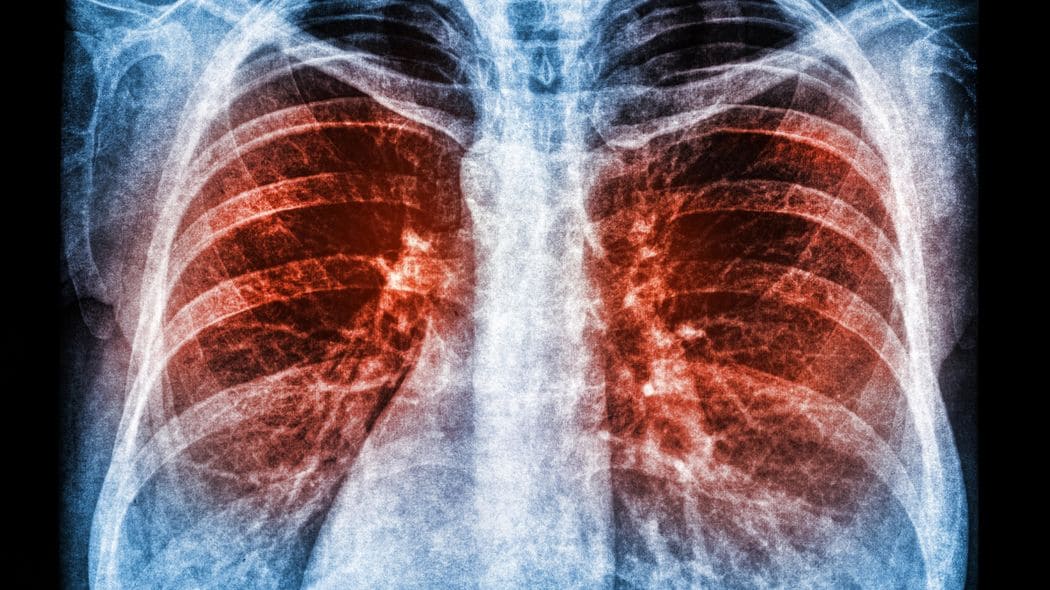

コロナ死4000人vs.例年のインフルエンザ関連死1万人、肺炎死10万人

インフルエンザの死者は、医師が死因をインフルエンザと認めた数であり、肺炎を併発したり、インフルエンザによって持病が悪化したりして亡くなった数は含まれない。インフルエンザに関連する死亡者数は年間約1万人と推計されている(関連死亡者数には、インフルエンザが直接的に引き起こす脳症や肺炎のほか、2次的に起こる細菌性の肺炎、また、呼吸器疾患や心疾患といった持病の悪化など、間接的な影響によって死亡した人の数も含まれる※)

それに対してコロナの場合、持病があるほど重症化しやすいとされており、全数とは言わないまでもコロナ感染で持病が悪化して亡くなった数も、「コロナ死」にカウントされていると思われる。そう考えるとインフルエンザのほうがコロナよりむしろ死者数は多いといえる。

例年、インフルエンザで3000人から1万人(持病の悪化も含む)亡くなることを知っている人であれば、もしくは、通常の肺炎で毎年10万人の命が奪われると知っている人であれば、コロナをここまで怖い病気と思わなかったかもしれない。